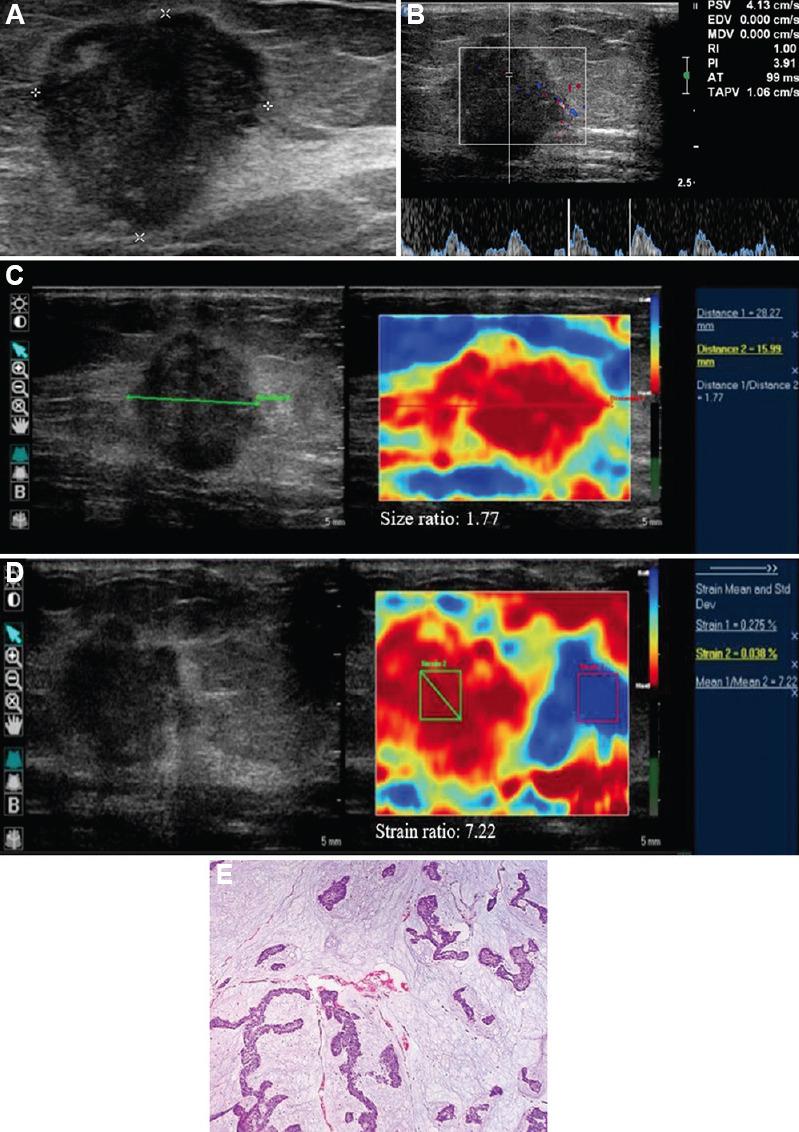

BACKGROUND & OBJECTIVES: : Ultrasound BI-RADS categories 3 and 4 constitute those breast masses which cannot be confidently classified as benign or malignant, owing to their morphological characteristics. These masses are further managed by follow up and biopsy, respectively. This study aims to evaluate the role of strain elastography and Doppler in better characterization of these sonographically indeterminate breast masses as benign or malignant.

: Fifty female patients with ultrasound BI-RADS 3 or 4 were evaluated with strain elastography and color Doppler including spectral analysis. Eight variables were assessed by elastography and Doppler, including a new phenomenon called bidirectional arterial flow (BAF). The findings were correlated with the gold standard diagnostic method of histopathology/cytology. Based on findings of combined elastography and Doppler method, the initial ultrasound BI-RADS categories of masses were re-categorized by up-gradation or down-gradation. Sensitivity, specificity, accuracy, positive predictive value, negative predictive value and receiver operating characteristic (ROC) curves were used to estimate the diagnostic performance of the combination method.

: Using ROC analysis, the positivity of ≥3 among the total eight variables correlated with malignancy on histopathology. Sensitivity, specificity and accuracy of the combination method using cut-off score ≥3 (i.e. at least three out of the eight parameters in the combination method being positive) for the prediction of malignancy was 100, 76.47 and 92 per cent, respectively, with the area under curve being 0.967. In addition, BAF was found predictive of malignancy with a diagnostic accuracy of 70 per cent.